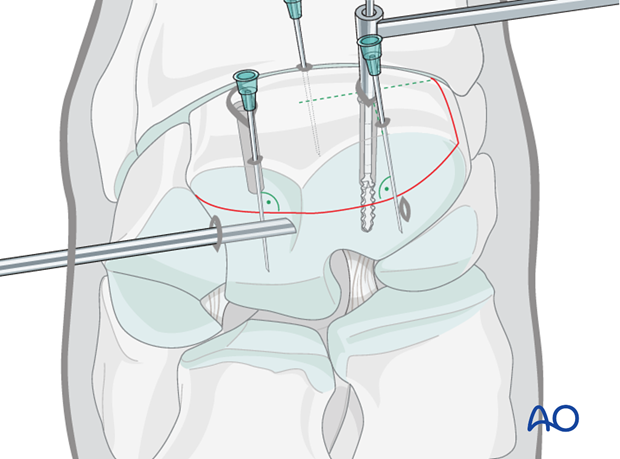

Two 4.5 mm glide holes are drilled through fragment until they enter the fracture line (the distance is predetermined by measurement by the radiographs).

The drill depths can be verified using an intraoperative radiograph.

The 3.2 mm drill guide is inserted into one glide hole and the 3.2 mm thread hole is drilled through the remaining third carpal bone. The hole is drilled through the entire parent third carpal bone so that maximal screw length can be used.

The first hole is countersunk at the dorsal surface and debris is flushed.

Correct screw lengths are determined using a depth gauge. The screws used are generally 36 mm long.

The first hole is tapped with a 4.5 mm tap protected by the corresponding drill guide. This should be done by hand.

The first 4.5 mm cortex screw of appropriate length is inserted and tightened under arthroscopic visualization.